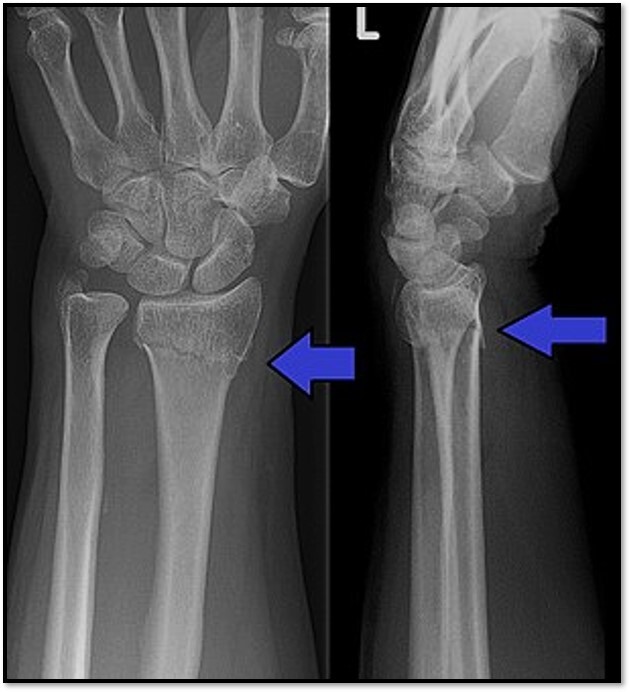

Q

What are the signs that a distal radius fracture is present?

A

Trabecular pattern, lucency, slight posterior angulation and cortical disruption anteriorly